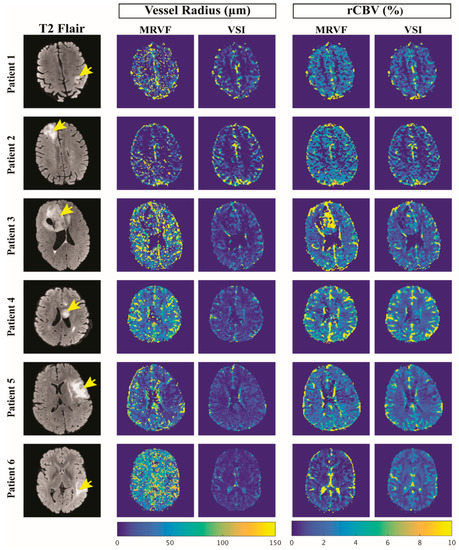

| Subject | Age | Sex | Diagnosis (Grade) | Molecular Profile | Tumor Type | k (10−3 s−1) | R (µm) | rCBV (%) | |||

|---|---|---|---|---|---|---|---|---|---|---|---|

| Mean | SD | Mean | SD | Mean | SD | ||||||

| 1 | 65 | M | Glioblastoma (IV) | IDH wild type | Enhancing | 1.5 | 2 | 12.88 | 14.84 | 2.49 | 1.55 |

| 2 | 54 | M | Oligodendroglioma (III) | IDH mutant, 1p/19q co-deleted | Non-Enhancing | 0.58 | 1.7 | 8.53 | 11.63 | 2.45 | 1.87 |

| 3 | 24 | M | Oligodendroglioma (III) | IDH mutant, 1p/19q co-deleted | Enhancing | 0.75 | 1.5 | 22.78 | 32.35 | 3.48 | 3.12 |

| 4 | 22 | F | Oligodendroglioma (II) | IDH mutant, 1p/19q co-deleted | Non-Enhancing | 0.41 | 1.2 | 34.64 | 29.36 | 3.17 | 1.38 |

| 5 | 37 | M | Astrocytoma (III) | IDH mutant | Enhancing | 0.5 | 1.4 | 17.83 | 20.75 | 2.42 | 0.85 |

| 6 | 28 | F | Astrocytoma (II) | IDH mutant | Non-Enhancing | 0.45 | 1.5 | 46.58 | 44.41 | 1.79 | 1.45 |

| Subject | Mean of Vessel Radius (μm) | Mean of rCBV (%) | ||||||

|---|---|---|---|---|---|---|---|---|

| Whole Brain | Tumor | Whole Brain | Tumor | |||||

| MRVF | VSI | MRVF | VSI | MRVF | VSI | MRVF | VSI | |

| 1 | 33.94 | 19.66 | 12.88 | 7.44 | 2.7 | 1.71 | 2.49 | 1.49 |

| 2 | 28.68 | 59.31 | 8.53 | 12.92 | 3.10 | 1.15 | 2.45 | 0.38 |

| 3 | 48.61 | 14.84 | 22.78 | 8.36 | 3.55 | 2.07 | 3.48 | 1.03 |

| 4 | 51.39 | 39.05 | 34.64 | 25.31 | 3.89 | 3.57 | 3.17 | 2.08 |

| 5 | 39.73 | 38.26 | 17.83 | 19.85 | 3.26 | 0.70 | 2.42 | 0.31 |

| 6 | 58.54 | 24.34 | 46.58 | 17.98 | 2.53 | 0.95 | 1.79 | 0.46 |

| Average | 43.48 | 32.58 | 23.87 | 15.31 | 3.17 | 1.69 | 2.63 | 0.96 |

| SD | 11.31 | 16.36 | 14.32 | 6.98 | 0.51 | 1.05 | 0.60 | 0.71 |